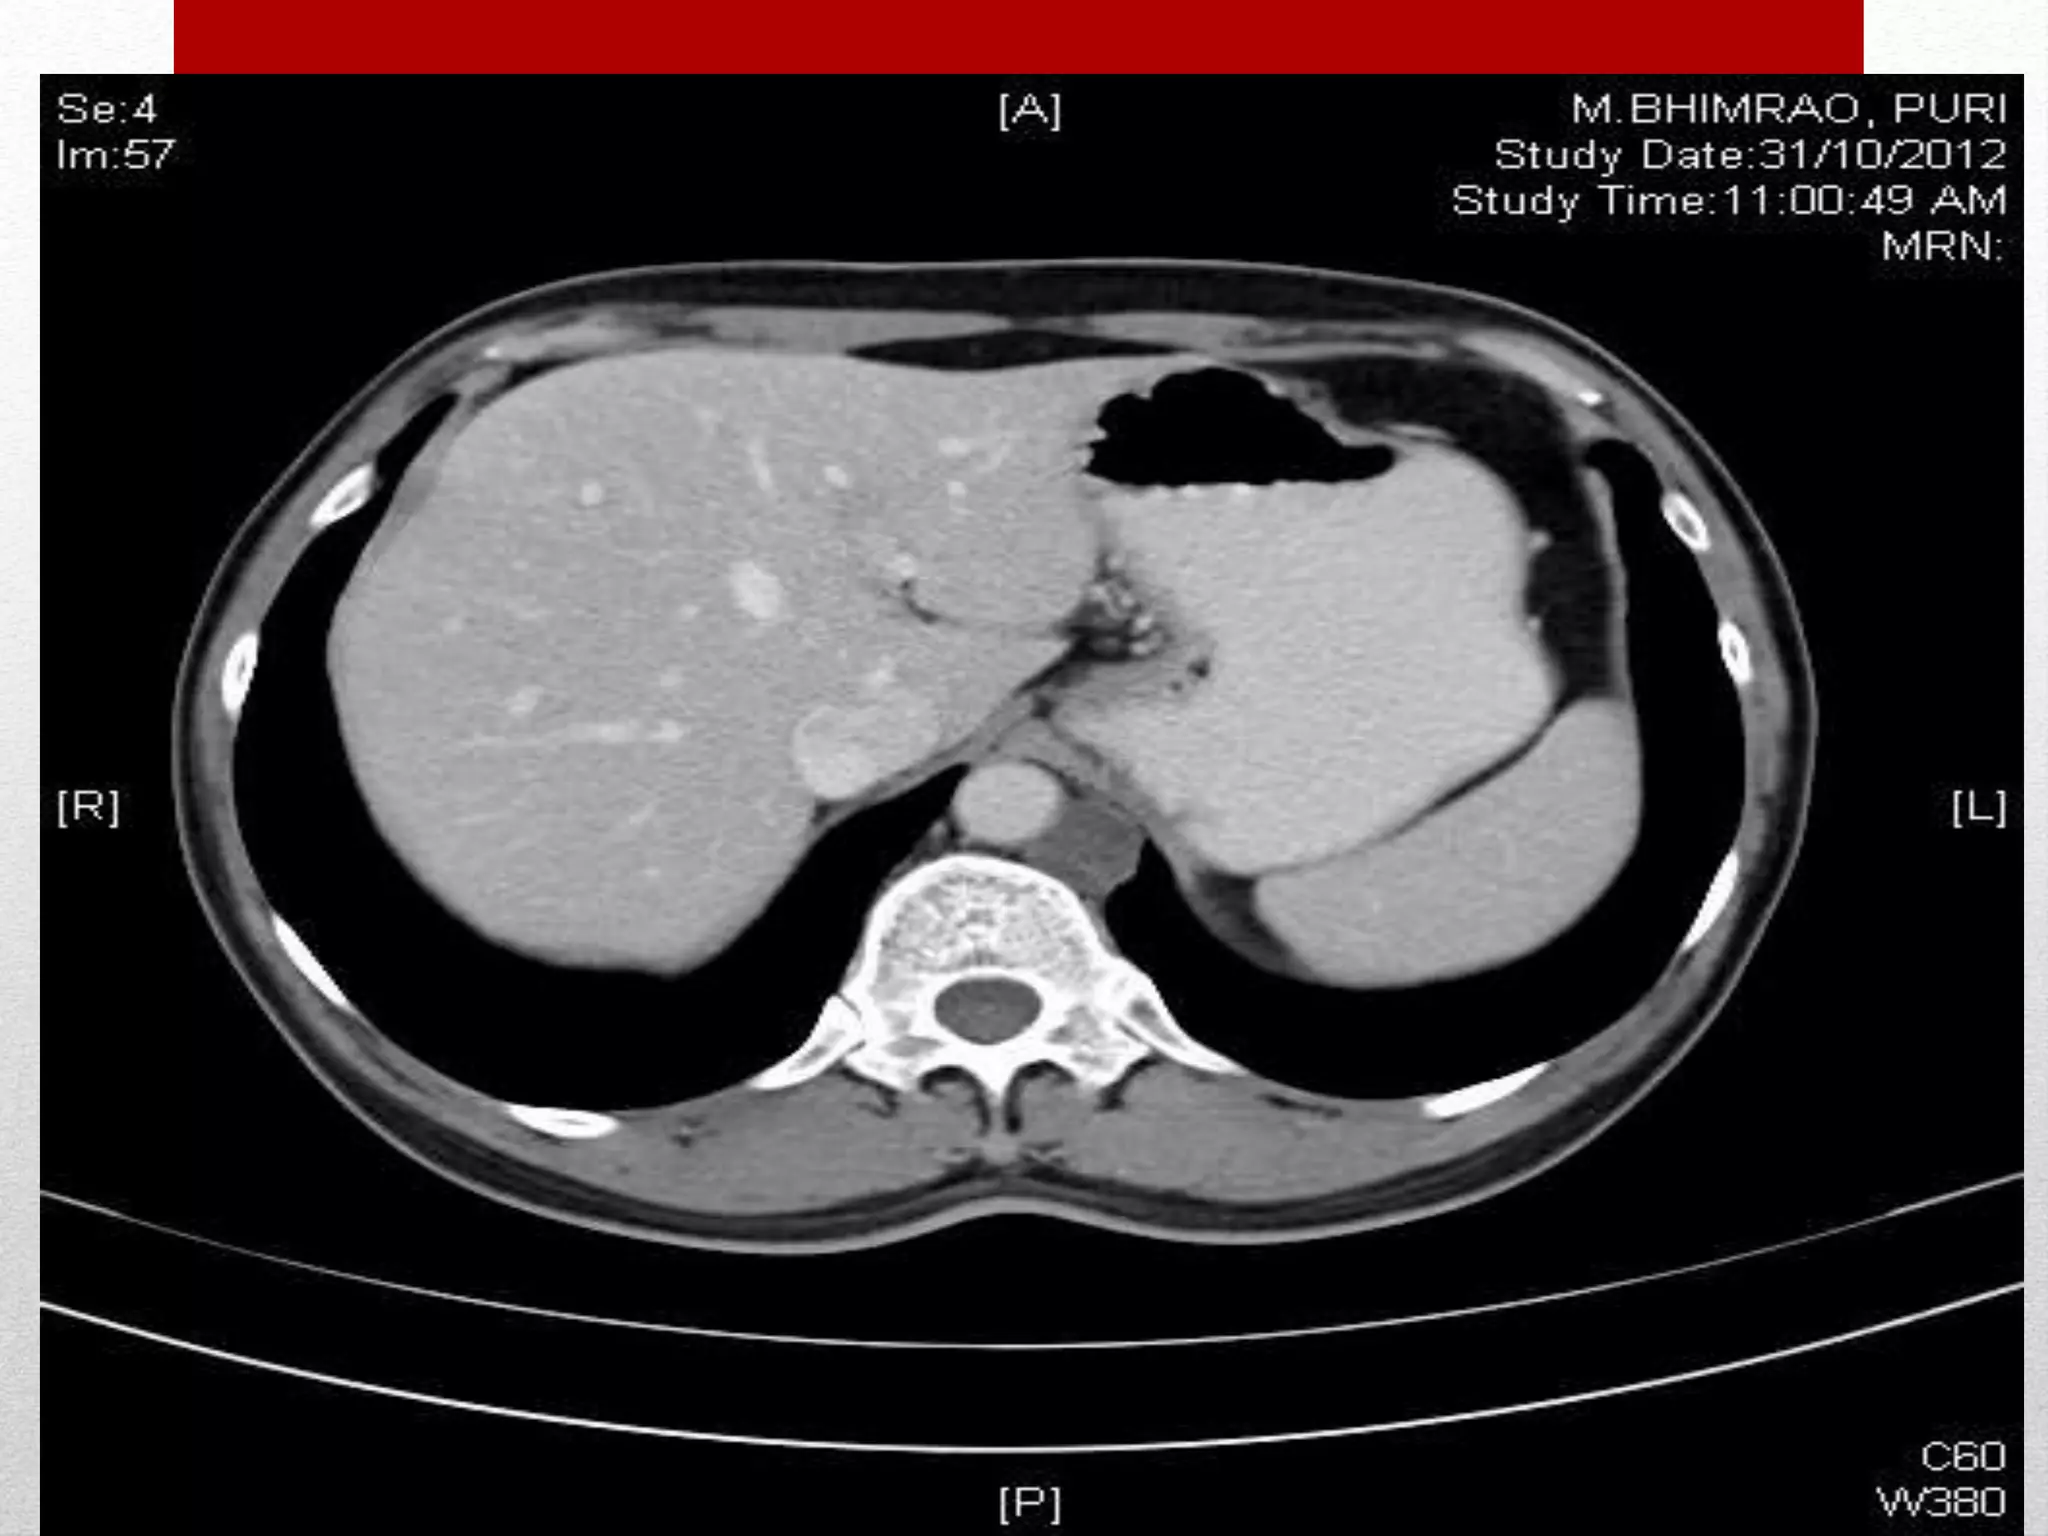

CHALLENGES IN RPLND

Retroperitoneal lymph node dissection kaushal